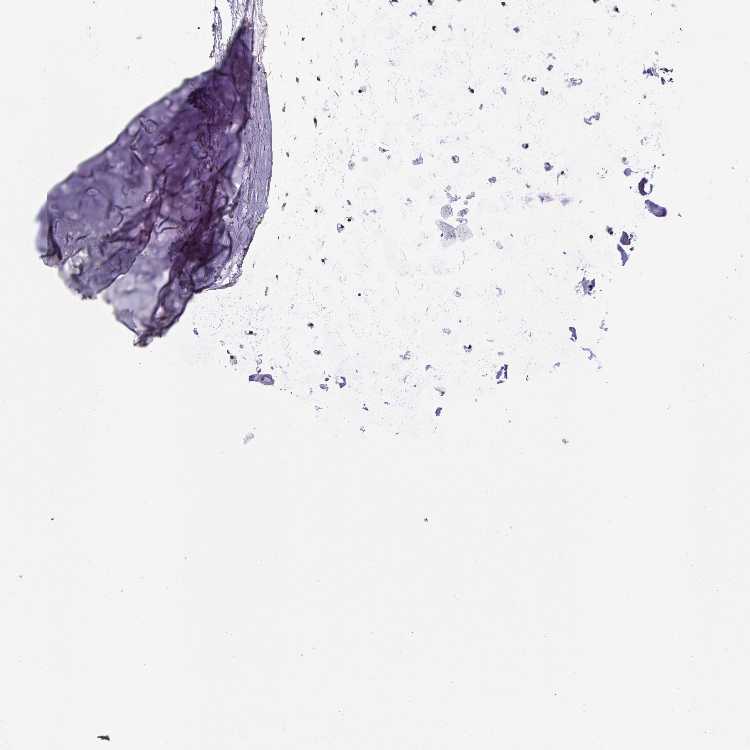

ADIPOSE TISSUE - Antibody stainingi

Antibody staining in the annotated cell types in the current human tissue is reported as not detected, low, medium, or high, based on conventional immunohistochemistry profiling in selected tissues. This score is based on the combination of the staining intensity and fraction of stained cells.

Each image is clickable and will lead to virtual microscopy that enables deeper exploration of all samples and also displays staining intensity scores, fraction scores and subcellular localization as well as patient and tissue information for each sample.

Antibody HPA052096Antibody HPA059714

Adipocytes Not detectedMedium